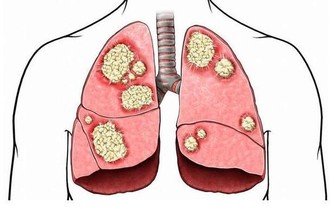

會。家族性高膽固醇血症是全球最常見的家族性遺傳疾病,由於基因突變身體代謝膽固醇的機制,導致壞的膽固醇(低密度脂蛋白膽固醇)濃度變高,罹患早發性心血管疾病的風險是一般成年人的20倍。父母之一若有家族性高膽固醇血症,孩子有50%的遺傳機會,因此,有家族史的高危險群應儘早就醫檢查。

不可以。低密度脂蛋白膽固醇透析術(俗稱洗血脂)是以洗腎的原理分離出血中的膽固醇,多用於治療家族性高膽固醇血症,這類患者的膽固醇可能高達300~400mg/dl,甚至飆過1000mg/dl以上,且以藥物控制的效果不顯著,而非用於預防高血脂。血脂透析多是每週進行一次,一次3~4小時,且須終身治療。

壞膽固醇(低密度脂蛋白膽固醇,LDL)是造成動脈硬化、阻塞的罪魁禍首,好膽固醇(高密度脂蛋白膽固醇,HDL)則扮演血管清道夫角色。因此,LDL應降得愈低愈好,但HDL數值,男性需高於40mg/dL,女性則要50mg/dL以上。